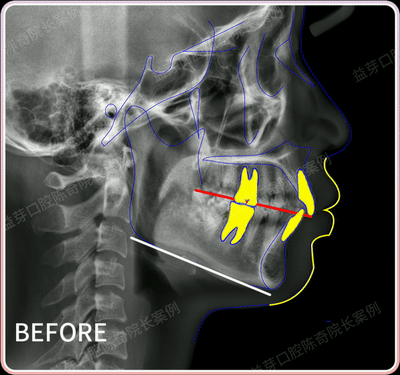

這個客人的主訴是解除牙列間隙,但是經過面診發現她還伴隨有中度的骨性前突,上前牙是非常直立的,回收時需要牙齒整體往回收。牙槽骨很薄,牙根的形態可以很明顯的看到(見圖二口內正面照)。

在考慮到客人的整體的美學改變,我為她設計了拔除兩顆上頜的第一前磨牙,和適當的擴寬牙弓的矯正方案。

在矯正的1年半時間裡,我們沒有打一顆骨釘,把隱適美牙套良好的控根效能發揮到極致。因為客人牙槽骨很薄,所以矯正過程中對上下牙控根移動的需求很重要。

這個案例我們不僅高效的解決牙齒前突和牙列間隙的問題,客人牙齦形態也有改善,顯得更飽滿。牙根內收後不會顯得突兀,客人的側貌也得到改善,下巴也更翹了,我們可以用隱形牙套很好地做到控根移動。

這個案例之所以能入選隱適美全球優秀案例,也是有諸多因素。除了患者要戴好牙套,更重要的是醫生的矯正方案,特別這種案例不透過打骨釘的前牙控根性內收,回收門牙時要準確控制好牙齒的移動方向和方式,保證牙根——尤其是牙神經血管出入的根尖始終保持在牙槽骨內側。

控根移動,學名叫轉矩移動,簡單來說就是牙冠基本不動,主要控制牙根移動。因為我們牙根是在牙槽骨內的,所以不能直接向牙根施力。我們需要藉助矯治器向牙冠施力,再透過控制力矩讓牙冠保持不動的基礎上,讓牙根朝計劃的方向和角度移動。控根移動也是所有牙齒移動中最難實現的。

控根移動主要是為了達到理想的矯正效果。在正畸前突拔牙案例中,控根內收是非常重要的一種內收方式,可以保持牙根與牙冠的整體向後移動,實現前牙最大程度上的內收。

比如上面這個案例,這位客人有中度的骨性前突,上前牙是非常直立的,這種情況就需要做控根內收。不僅能有效解決嘴突的情況,還能避免常規牙齒移動後,牙冠內收但牙根依然凸出的問題。

因為我們戴牙套施加的力量是在牙冠上,從力學分析上講,牙齒會發生傾斜運動,也就是牙冠移動的多,牙根移動的少。但控根移動與它正好相反,牙冠基本不動,牙根發生移動,所以這對施力大小、施力方式、組織的應力分佈等等有極高的要求。

很多時候我們會透過打骨釘來改變施力方式,控制施力大小。但上面這個案例陳院長利用隱適美的優勢,不需要打骨釘就能控根內收。在客人牙槽骨本身就薄弱的情況下控根移動,並能保證牙齦和牙根的健康,真的太厲害了。